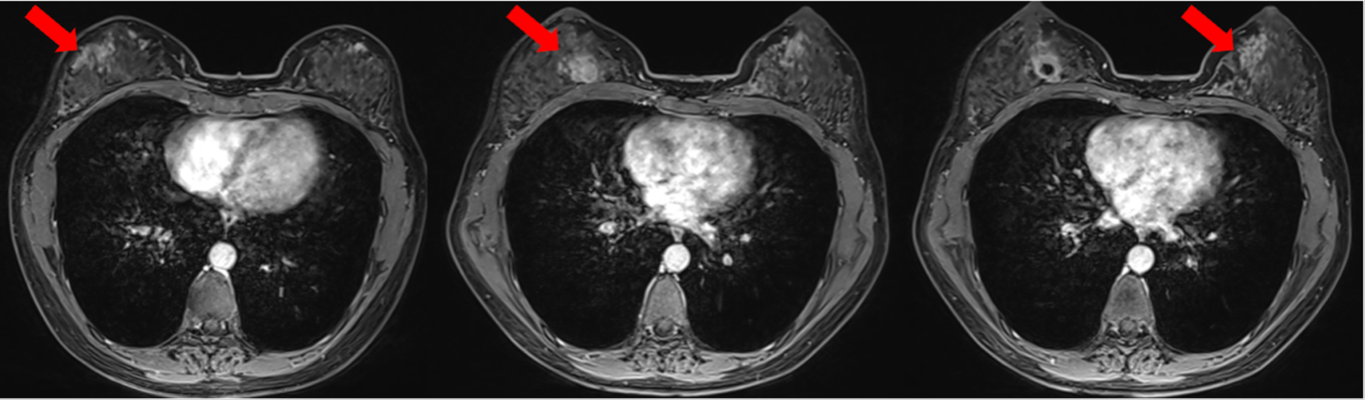

疗效评价:肝脏病灶明显缩小,最佳疗效PR,PFS>11个月。

肝脏转移瘤(较大者)缩小情况

0926-04.png

RC48(维迪西妥单抗)是我国自主研发的新一代HER2靶向抗体药物偶联物。该药物由高亲和力的Disitamab抗体、可裂解连接子及强效微管抑制剂MMAE构成。其优化的药物抗体比值在确保高效抗肿瘤活性的同时,显著降低了系统性不良反应,实现了疗效与安全性的良好平[16]。RC48-C001/C003研究证实了RC48在HER2低表达乳腺癌治疗中的有效性。该研究纳入的晚期患者中,56.1%伴有肝转移;在此类患者群体中,采用2.0 mg/kg、每两周一次的剂量方案单药治疗,客观缓解率(ORR)达到33.3%,疾病控制率(DCR)高达81.8%[3]。本文病例二线治疗采用RC48带来了符合预期的优异获益:肝转移病灶持续缩小(较大者长径由20mm缩至5mm),疗效评价达PR,至今二线PFS已超11个月。期待未来更多前瞻性研究来验证RC48在HER2低表达伴肝转移乳腺癌治疗中的价值,进一步拓展其适应症范围,为更多患者带来福音。